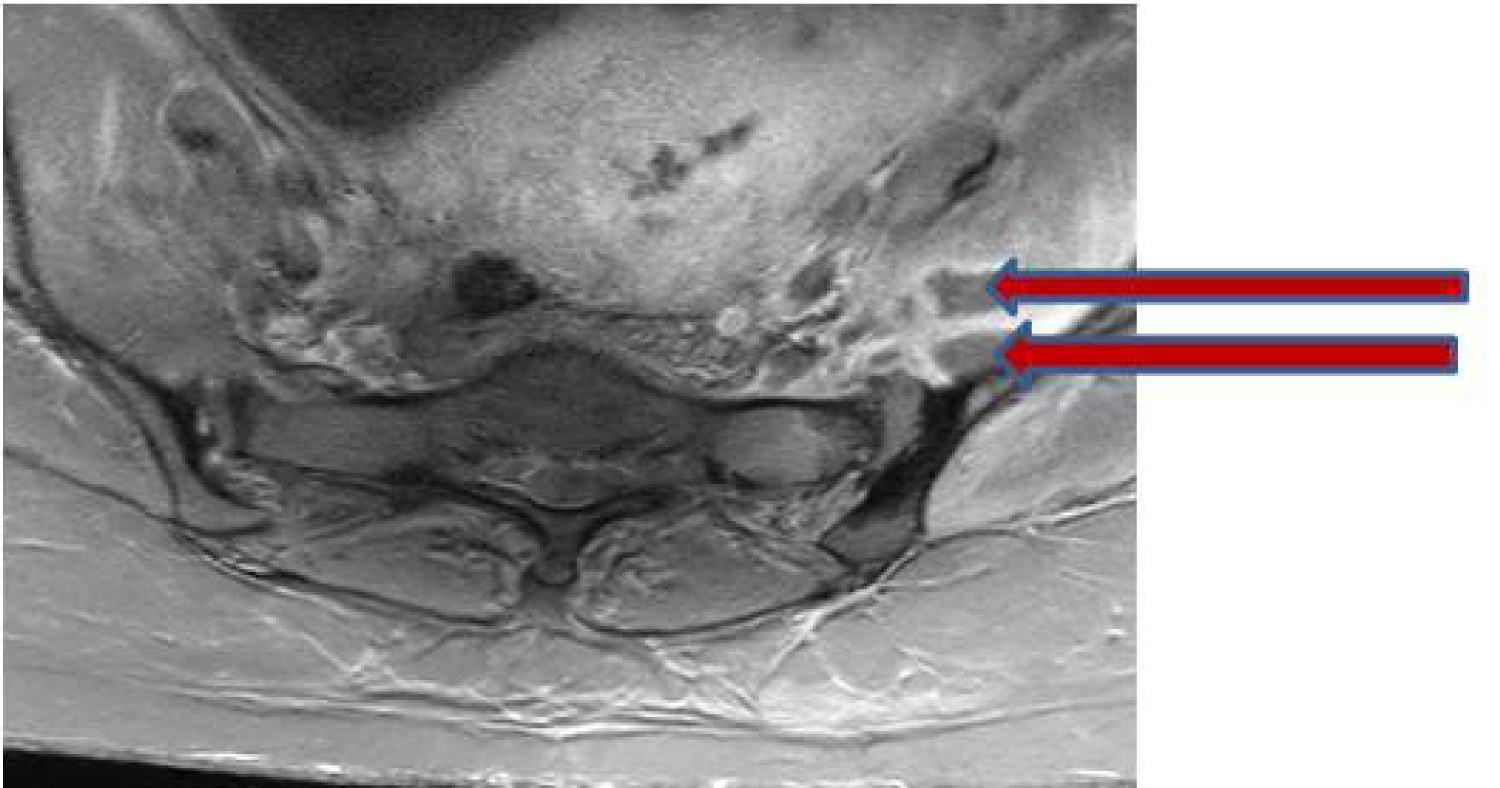

In light of recent epidural catheter placement, an urgent magnetic resonance imaging (MRI) of the lumbar spine with contrast enhancement was ordered. No evidence of epidural hematoma or abscess was present. However, incidental findings of asymmetric fluid distention of the left sacroiliac (SI) joint (Figure 1) with fluid collections within the left iliopsoas, left piriformis, and left gluteus muscles (Figure 2) were detected, findings concerning for infectious/inflammatory sacroiliitis (ISI). Neuroradiology consult was placed, and under computerized tomography (CT) guidance, about 10 ml of purulent fluid was aspirated from left SI joint, and sent for Gram stain and culture. Infectious Disease consult was placed and the patient was started on empiric vancomycin pending culture results. Further work up included measurement of erythrocyte sedimentation rate (ESR), and C-reactive protein (CRP), both were found to be about three fold elevated. Blood cultures were drawn but reported later as negative for any growth. Gram stain of SI joint fluid revealed Gram positive cocci that on culture were identified as group B streptococci (Strep. agalactiae). Vancomycin was changed to ceftriaxone per sensitivity results. An orthopedic consult for septic arthritis was also placed, but conservative management was recommended in light of clinical (decreasing pain), and laboratory (resolving leukocytosis, decreasing ESR and CRP) improvement. The patient was discharged home on long term (6 weeks) intravenous antibiotics and recommended to follow up as instructed.

Figure 2: Fat saturated T1-weighted axial image demonstrates peripherally enhancing fluid collections within the left iliopsoas muscle (red arrows). View Figure 2